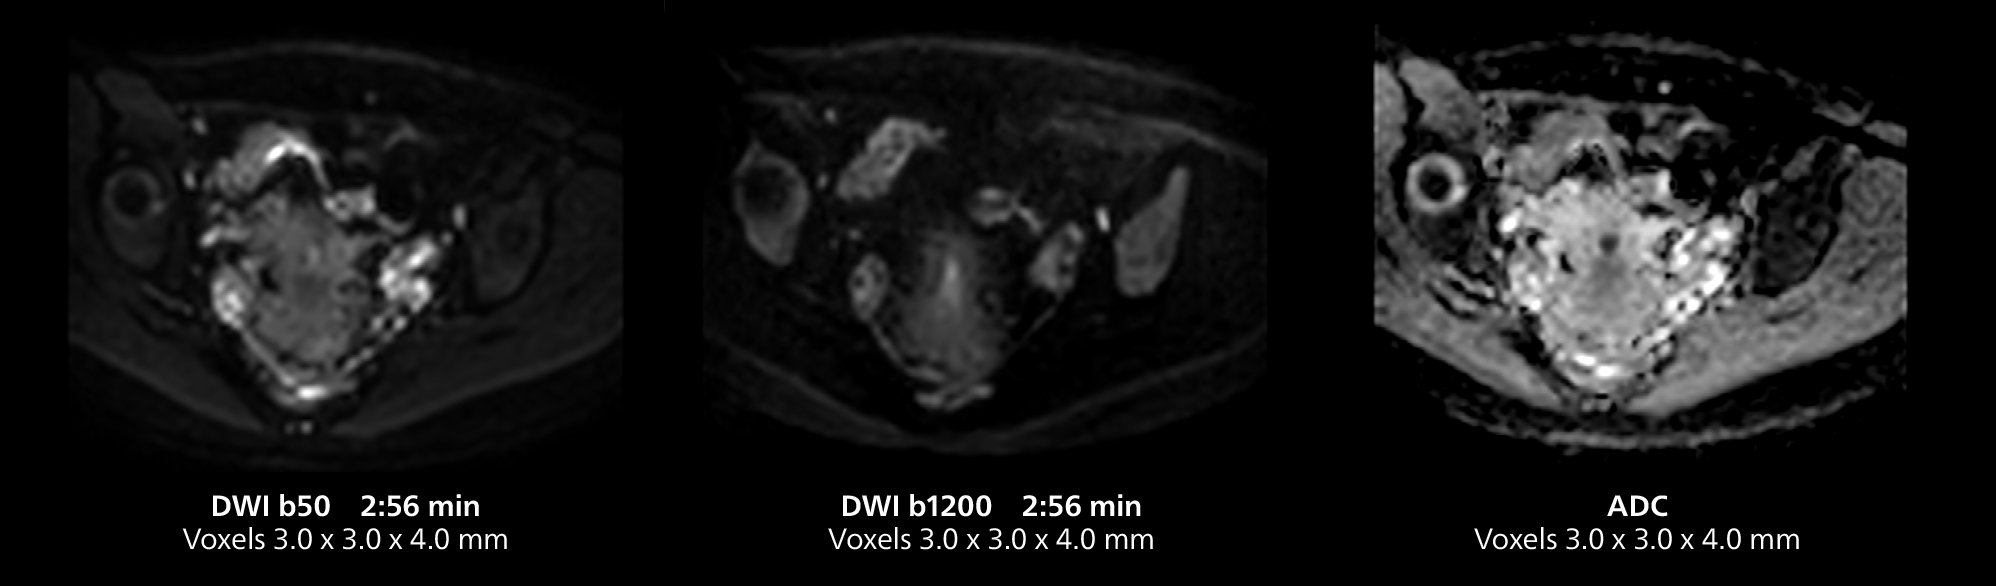

The isotropic high resolution 3D sequence in this MRI case allows for reformatting to obtain other orientations with high quality. Acquired on the MR 5300 system.

Dr. Gellée highlights the robust free-breathing scans as “the feature that makes the biggest difference in my daily work. The 3D free breathing sequences are very reproducible, and the axial acquisition is very good. For example, in endometriosis, which is one of my focus areas, it provides high contrast and good resolution so that I can see small details. We also use free breathing for liver and pancreas imaging. In multi-phase liver studies, 4D Free Breathing delivers 3-second temporal resolution, making a dynamic scan with more than one arterial phase possible.”

This MRI case illustrates good resolution and imaging quality obtained within reasonable scan times using the MR 5300 1.5T system with the anterior torso cardiac coil that allows use of a large field of view (FOV).